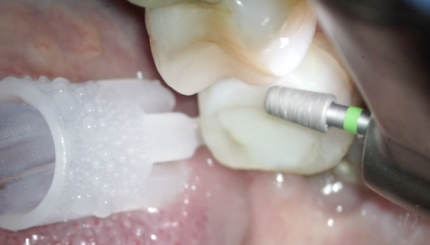

25 26. ФИНИШНОЕ ПРЕПАРИРОВАНИЕ ПОД КОРОНКУ, РЕТРАКЦИЯ, ОТТИСК